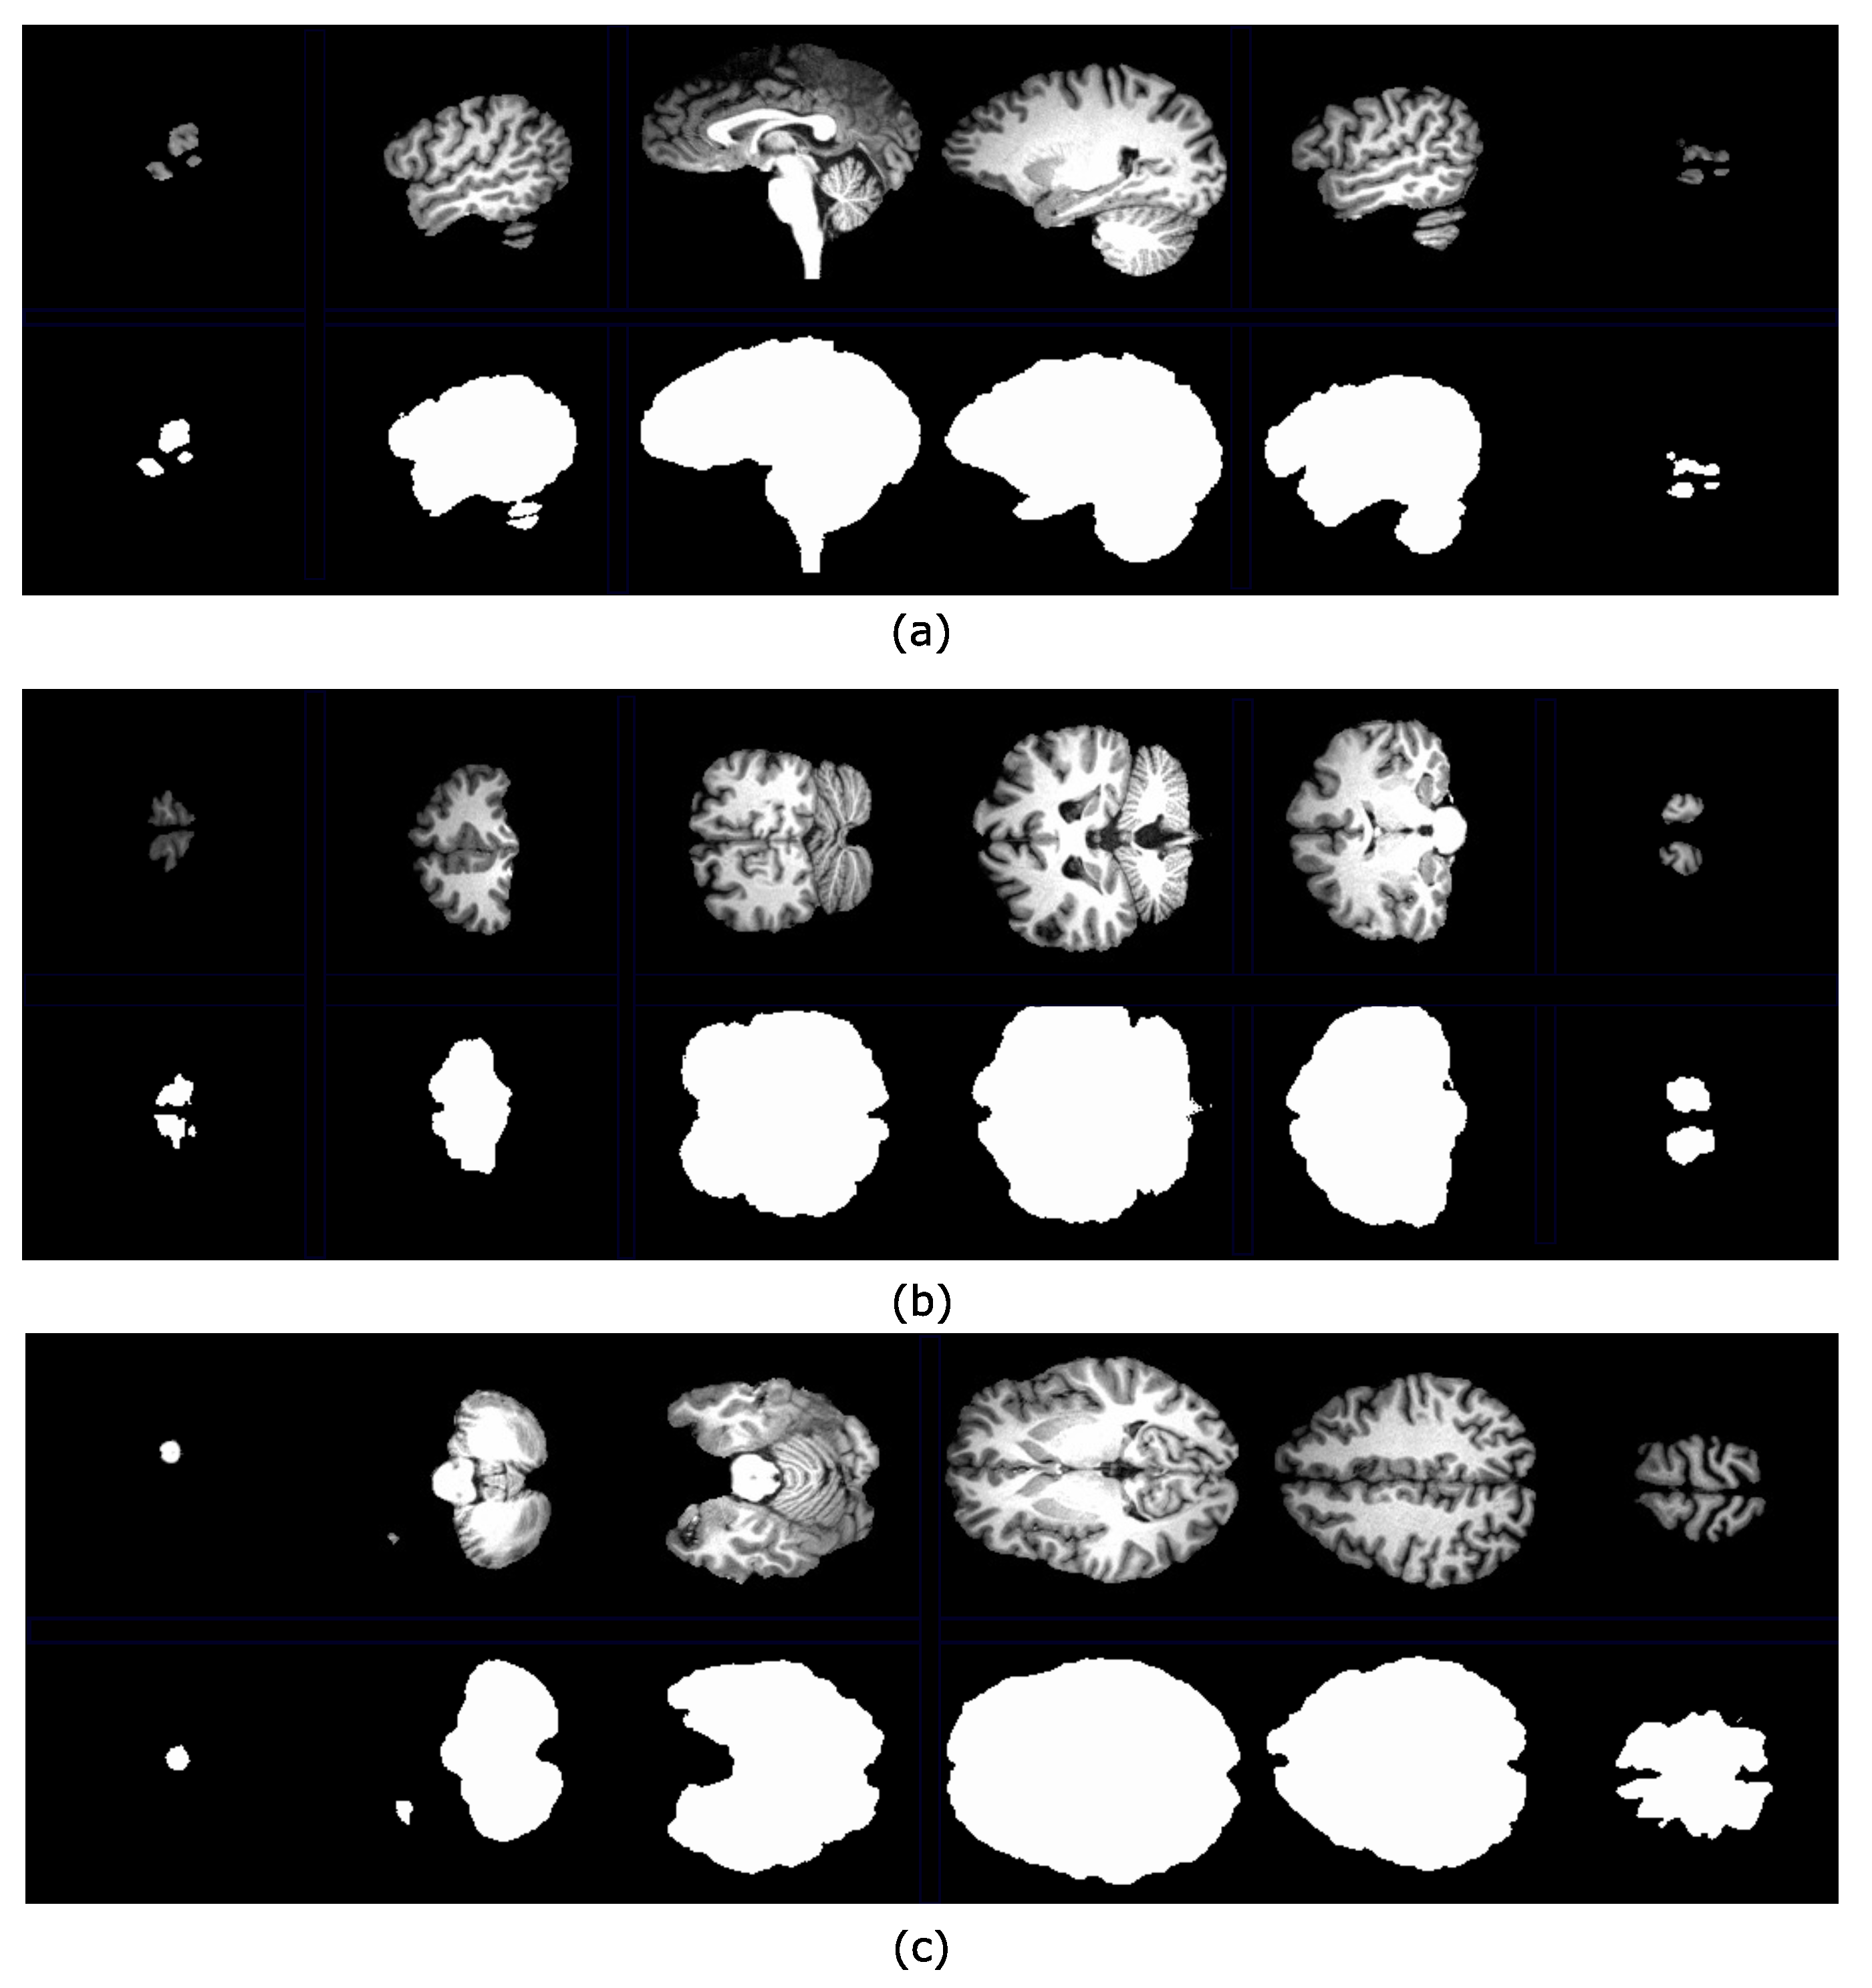

4.2. Brain Extraction Based on Hyperconnected Functions and Lower Leveling